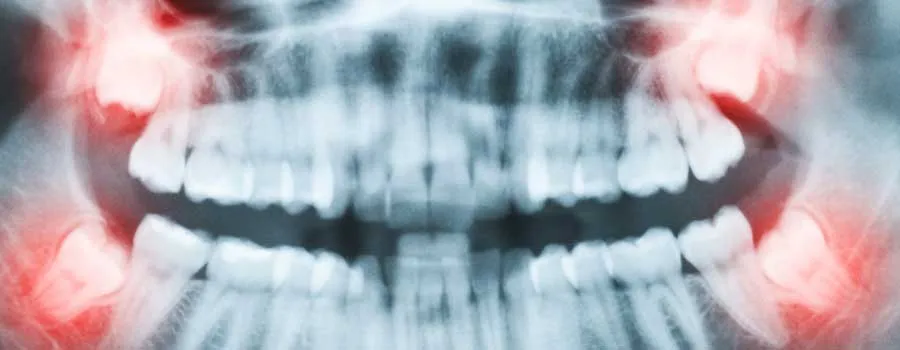

Les dents de sagesse, également appelées troisièmes molaires, sont les dernières dents à apparaître dans la bouche humaine, généralement à la fin de l’adolescence ou au début de l’âge adulte. Ces dents sont situées à l’arrière de la bouche, une de chaque côté de la mâchoire supérieure et de la mâchoire inférieure, et sont généralement les dernières à émerger.

La plupart des gens ont quatre dents de sagesse, deux sur la mâchoire supérieure et deux sur la mâchoire inférieure. Mais certaines personnes peuvent en avoir moins ou pas du tout, et dans de rares cas, certaines personnes peuvent en avoir plus.

Aujourd’hui, ces dents sont souvent considérées comme des structures vestigiales, c’est-à-dire qu’elles n’ont aucune utilité réelle et peuvent même causer des problèmes tels que l’encombrement ou l’inclusion. C’est pourquoi de nombreuses personnes se font retirer leurs dents de sagesse par le biais d’une opération de chirurgie dentaire.